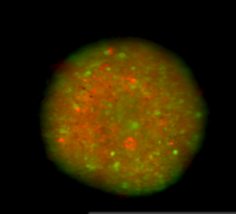

Spheroid Cytotoxicity. Image Credit: Scintica Instrumentation Inc.